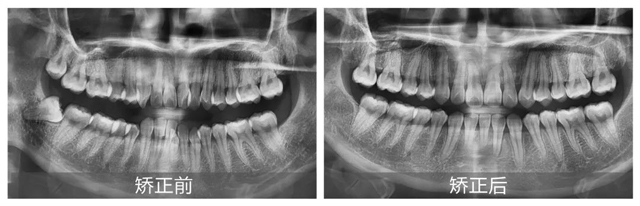

經(jīng)過詳細面診,并根據(jù)口掃、CBCT檢查結(jié)果顯示,鄧女士主要面臨的問題有上頜牙列中度擁擠、下頜牙列重度擁擠,并且有一顆下切牙由于長期的擁擠已經(jīng)出現(xiàn)牙周炎癥狀。

郝璐醫(yī)生指出,因為牙齒過于緊密,鄧女士的下前牙排列錯位,形成了咬合創(chuàng)傷,同時伴有牙槽骨吸收和牙齦萎縮的情況。此外,上頜左側(cè)切牙和右側(cè)尖牙反頜,造成了上下頜牙弓不對稱,上下頜中線不一致,前牙深覆合。這些情況在鄧女士張口說話時很容易就能注意到,嚴重影響了面部美觀。

郝璐醫(yī)生表示,針對鄧女士的情況,治療的主要目標是解除牙列擁擠情況,調(diào)整反頜關系,消除咬合創(chuàng)傷,從而改善整體口腔健康狀況。

經(jīng)過一年零三個月的精心矯正,在取下牙套的那一刻,鄧女士不僅圓了兒時的夢想,更重拾了那份因自信笑容而帶來的快樂:“這一切都是值得的,每天看著變得這么好看的牙齒,感覺自己整個人都不一樣了!”